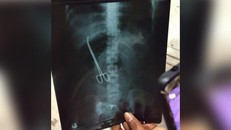

Hình ảnh chiếc kéo bị bác sĩ bỏ quên 3 tháng trong bụng bệnh nhân

Đau bụng dữ dội, cô gái đi khám phát hiện chiếc kéo nằm trong bụng đã 3 tháng

Bệnh viện đã thực hiện một cuộc phẫu thuật miễn phí để lấy chiếc kéo ra khỏi bụng cô gái.